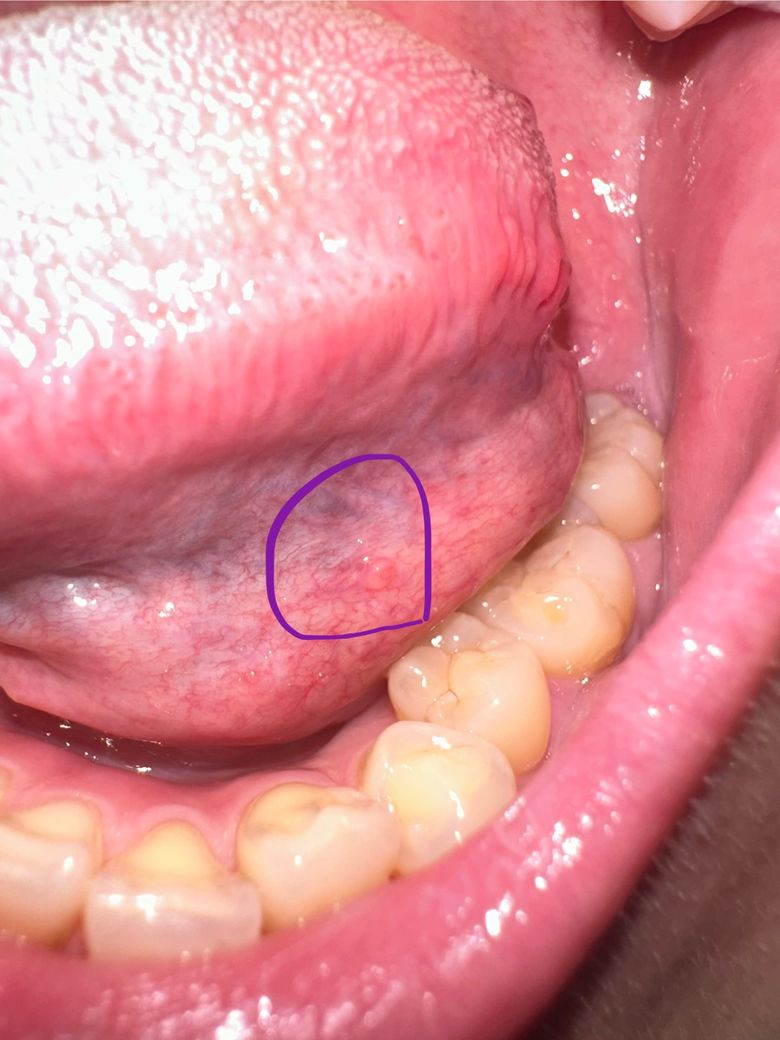

사진처럼 혀 왼쪽 아래 쪽에 볼록 뭔가 생겼어요!!

양쪽 동일하지는 않아요!!

통증도 없고 딱딱하지도 않아요!!

살짝 가끔뭐가 있다?는 느낌을 받아요

• 2번 째 사진

설명하신 위치와 증상으로 보면, 병적인 병변보다는 정상 구조이거나 양성 변화일 가능성이 높습니다.

2. 정맥 확장(설하 정맥, 정맥류)

혀 아래쪽에 비교적 흔하며, 자세나 혈류에 따라 한쪽이 더 튀어나와 보일 수 있습니다.